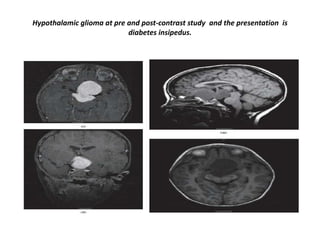

Hypothalamic glioma at pre and post-contrast study and the presentation is

diabetes insipedus.